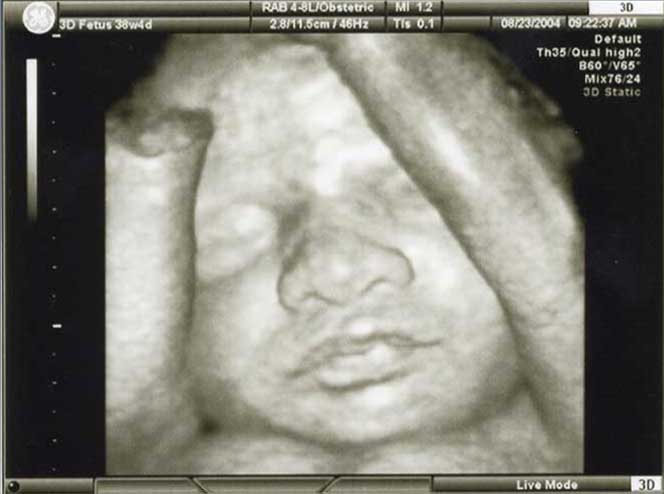

3D/4D HD LIVE

Στο ιατρείο μας προσφέρουμε υψηλής ευκρίνειας 3D και 4D τεχνολογία απεικόνισης του εμβρύου. Η τεχνολογία αυτή αποτελεί ένα ακόμα σημαντικό διαγνωστικό όπλο στη φαρέτρα του προγεννητικού ελέγχου, ενώ ταυτόχρονα ενισχύει την ανάπτυξη του δεσμού ανάμεσα στους μελλοντικούς γονείς και το μωρό τους.